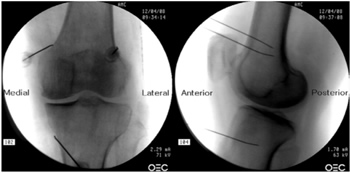

Figura 1